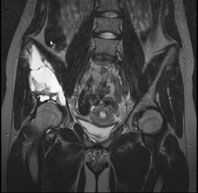

Ein 13-jähriges Mädchen kommt humpelnd zu Ihnen in die Praxis mit Schmerzen in der rechten Hüfte, die seit einigen Monaten bestehen und besonders bei Belastungen auftreten. Eine sichtbare Schwellung besteht nicht, kein Sturzgeschehen in der Anamnese.

Die Röntgenuntersuchung von Becken/Hüfte zeigt eine septierte geographische Osteolyse in der Ala und im Korpus des Os Iliums rechts. Das Röntgenbild und die Aufnahmen der nachfolgenden MRI-Untersuchung sehen Sie hier:

Frage Welche Diagnose stellen sie aufgrund der vorliegenden Bilder?